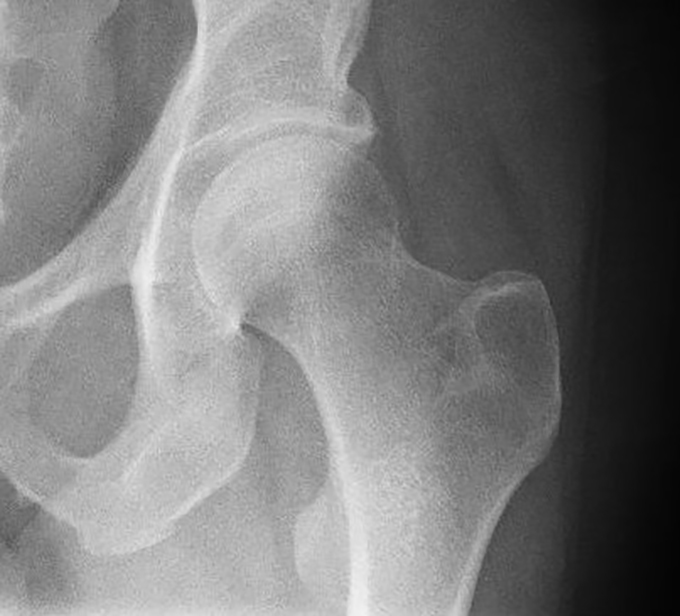

Managing Hip Fractures during COVID19

Neck of femur fractures are usually a mainstay of admissions to orthogeriatric services. A recent review of this with recommendations around surgery, in light of the current COVID-19 pandemic, has recently been released by NHS England.

• Hip fracture surgery is likely to be one of the most common major operations undertaken during the coronavirus pandemic and is used as the example in these guidelines, but the principles should be applied as appropriate to other injuries in older people;

• Most hip fractures occur in the home and the social isolation policy will not prevent these. A significant reduction in the incidence of hip fracture is not anticipated;